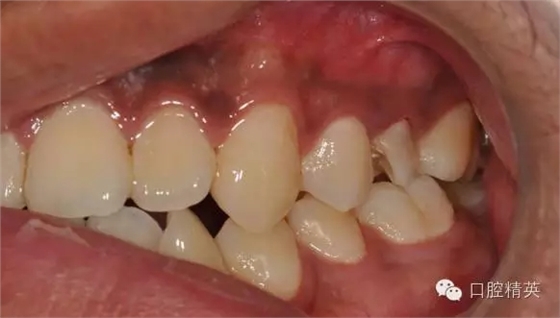

檢查:25近中鄰頜面暫封物,叩痛(-),無(wú)松動(dòng),牙髓活力喪失,牙齦顏色正常

診 斷:25牙體缺損

圖2修復(fù)前咬頜觀